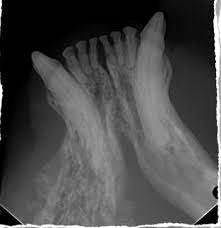

Oral Tumors Animal Dental Specialist from animaldentalspecialist.com It causes difficulty breathing, snorting, sneezing, coughing and nasal secretions. Lymphoma is by and large the most common cancer that affects cats, although there are other types of feline cancers that can affect domestic cats. The lymph nodes behind the knees and under the jaws are easiest to find. For most oral tumors in cats and dogs, we do not know the underlying cause or ways to prevent occurrence. Lymphoma typically happens in older felines and most commonly occurs in the small intestines, says dr. 12 warning signs of cancer in cats. Please understand that these are just potential warning signs and should not panic you, but prompt a visit to your veterinarian. If your cat is eating less but seems to be bulking up, take a trip to the vet, says rocha.

Brushing your pet's teeth every day not only helps keep your pet's teeth and gums healthy—it will also familiarize you with your pet's mouth. Unusual lumps or swellings anywhere on your cat's body, especially if they're getting larger or changing shape.; Cancer in cats is the leading cause of death among cats. When cancerous cells or tumors are present in the nasal cavities or sinus passages, the symptoms often mimic those of a respiratory infection. Top 10 warning signs of cancer in your pet. Oral pain is usually apparent, especially in cats with tumors that have penetrated the underlying bone. Clinical signs of oral cancer. The three most common signs of a malignant oral tumor are: A simple palpation (examination by touch) will indicate whether the lymph nodes under your cat's jaw and along its neck are enlarged, a confirmation of which would indicate that the body is fighting a diseased condition (as the lymph nodes produce white blood cells). Please understand that these are just potential warning signs and should not panic you, but prompt a visit to your veterinarian. Owners may notice a mass in the cat's mouth. Cats suffering from oral tumors often develop jaw cancer or cancer in the oral cavity. Respiratory, nasal or pulmonary carcinoma is most common in the muzzle and lung cancer in cats.

Cancers Tumors In Cats Hill S Pet from www.hillspet.com One of the most common symptoms of cat cancer are lumps and bumps. unusual lumps that change size could be a sign of cancer. Squamous cell carcinoma in cats is unique in that we know that exposure to cigarette smoke is a strong risk factor. Symptoms of mouth cancer in cats mouth cancer in cats may be noted by a visible tumor or mass of the oral cavity. Cats are extremely good at hiding signs of pain and cancers of the oral cavity can go unnoticed for some time. Cancer in cats can be very difficult to find, as cats can easily hide their pain. Gingival fibrosarcoma commonly presents with excessive salivation, halitosis, difficulty picking up food, difficulty chewing, loose teeth, oral growths, weight loss and, at times, bleeding from the mouth. Squamous cell carcinoma is the most common oral cancer in cats. Oral pain is usually apparent, especially in cats with tumors that have penetrated the underlying bone.